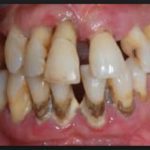

В зависимости от течения выделяют острый периодонтит и хроническую форму. Первый бывает гнойным, серозным, исходя из типа инфекции. Для хронического варианта характерно разделение на три группы: фиброзный, гранулирующий и гранулематозный если ткань около зуба уплотняется, говорят о фиброзной форме. При разрастании соединительной ткани на фоне воспаления речь возникает гранулированный периодонтит. Если очаг воспаления выглядит как замкнутая полость с гноем, которая постоянно увеличивается, постепенно разрушая ткань зуба, диагностируют гранулематозный вид.

Стоматологи выделяют три степени протекания болезни. На первой и самой легкой стадии образуется карман в десне глубиной до 4 мм. Пока ощущения неприятные, но терпимые. Изменения в костной ткани еще не начались. Средняя степень тяжести характеризуется увеличением глубины кармана до 6 мм. Такой периодонтит симптомы имеет более явные: корни зубов слегка оголяются, десны воспалены, зубы становятся подвижными. Тяжелая стадия – это карман глубиной уже до 9 мм, сильное нагноение. Зубы меняют свое положение, а их подвижность настолько сильная, что не позволяет нормально питаться.

Гранулирующий периодонтит вызывает сильную боль в пораженном зубе, отек десны, при котором она может приобрести даже синий оттенок. Болевые ощущения возникают в форме приступов и усиливаются при жевании или температурном воздействии (когда человек ест мороженое, пьет горячий чай). Обострение периодонтита провоцирует формирование свища с серозным или гнойным содержимым. Его ход открывается на шее или лице, и после разрыва образования с последующим оттоком гноя возникает временное облегчение, после чего болезнь переходит в хроническую фазу.